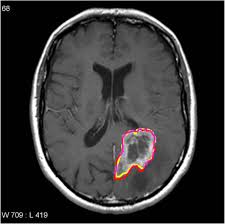

- Medical imaging plays a pivotal role in diagnosing and planning treatment for brain tumors, which affect millions globally. Accurate segmentation and classification of brain tumors from medical images are crucial to assist clinicians in understanding tumor characteristics.

- A client required an AI-powered solution to improve brain tumor diagnosis. The main challenge was the time-consuming and complex manual process of delineating tumor boundaries and classifying different tumor types. The objective is to explore 2D Image Segmentation using neural networks for brain tumor classification and segmentation.

- The AI-powered brain tumor segmentation solution significantly improves diagnostic accuracy, reducing manual effort and analysis time.

- Clinicians benefit from enhanced workflow efficiency, faster tumor identification, and improved treatment planning.